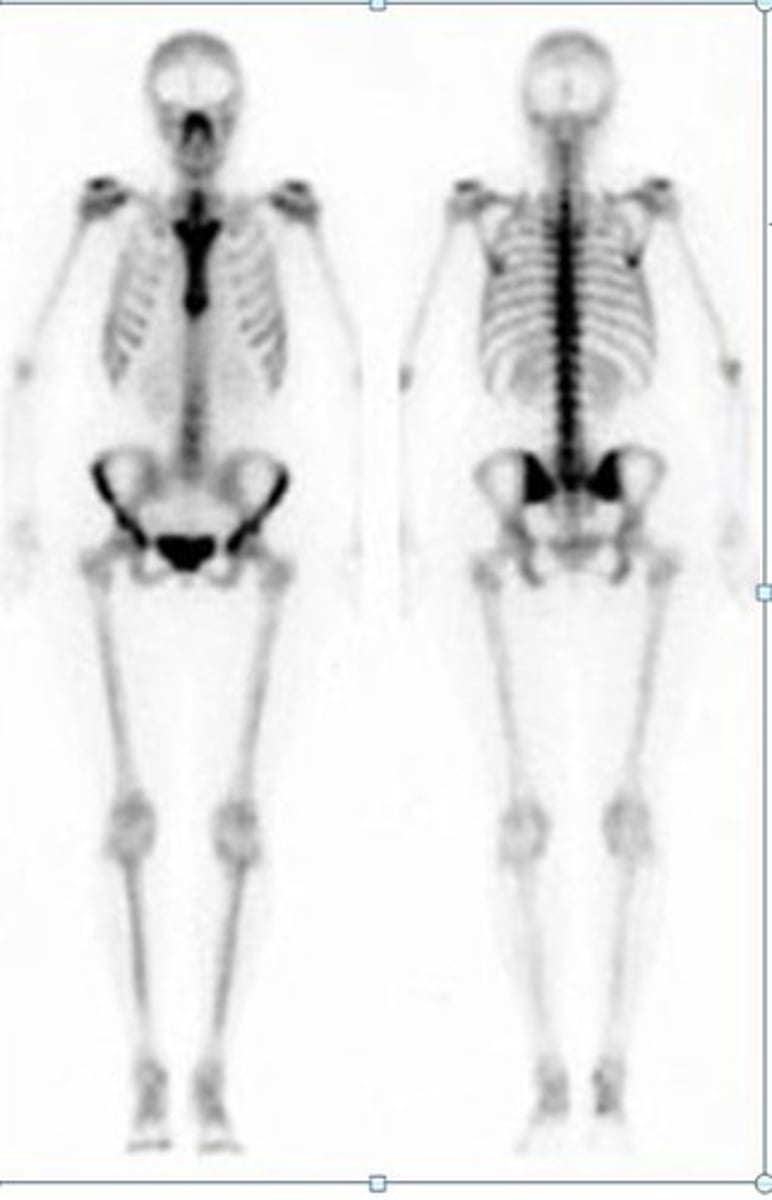

Bone scan

<p>Looks at the skeletal system</p><p>-Radioactive phosphate coupled to technetium-99 (taken up by osteoblast &amp; incorporated into bone --&gt; scanned 3 hours later)</p>

When should you order a bone scan?

Bone metastasis, osteomyelitis, trauma/fractures, metabolic bone diseases, avascular necrosis, arthritic disease